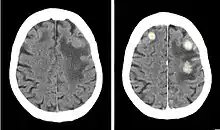

Iobitridol is an iodine-containing radiocontrast agent.[2][5] The iodine atoms readily absorb X-rays, resulting in better contrast in radiography images.[9] The quality of images made with this drug is equally good as with other low– or medium–osmolarity iodinated contrast agents such as iopamidol or iohexol.[5]